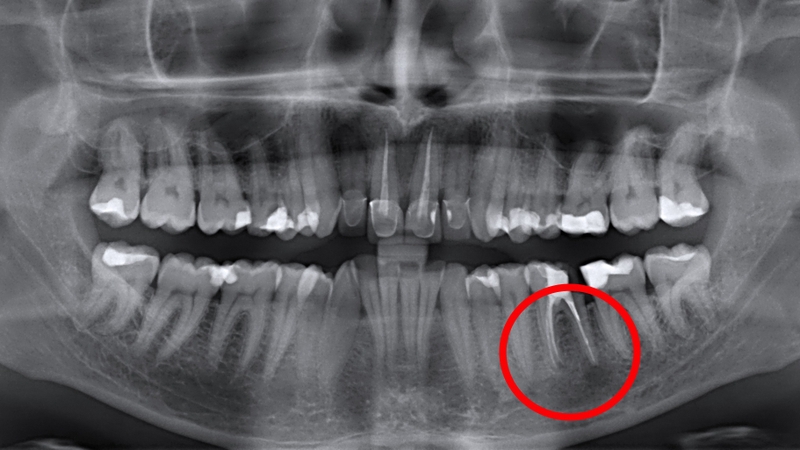

Đây là tình trạng viêm xảy ra tại khu vực xung quanh chóp răng. Bệnh lý này có thể được phân loại thành hai dạng: Dạng không có triệu chứng (asymptomatic) và dạng có triệu chứng (symptomatic). Viêm không triệu chứng thường tiến triển âm thầm và có thể gây tổn hại cho các mô xung quanh nếu không được điều trị kịp thời. Ngược lại, viêm có triệu chứng thường gây đau đớn khi nhai hoặc khi tiếp xúc với răng bên cạnh và thường xuất hiện đột ngột.

Là một trong những tình trạng khẩn cấp nha khoa phổ biến nhất, áp xe chóp răng xảy ra khi vi khuẩn xâm nhập vào tủy răng và gây nhiễm trùng. Tình trạng này có thể dẫn đến đau đớn dữ dội, sưng tấy, có thể gây ra các biến chứng nghiêm trọng nếu không được điều trị kịp thời.